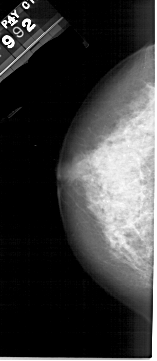

A_1222_1.RIGHT_CC

RIGHT_CC LINES 4711 PIXELS_PER_LINE 2221 BITS_PER_PIXEL 12 RESOLUTION 43.5 OVERLAY

FILE: A_1222_1.RIGHT_CC.OVERLAY

TOTAL_ABNORMALITIES 1

ABNORMALITY 1

LESION_TYPE MASS SHAPE ARCHITECTURAL_DISTORTION MARGINS SPICULATED

ASSESSMENT 5

SUBTLETY 5

PATHOLOGY MALIGNANT

TOTAL_OUTLINES 2

BOUNDARY

CORE